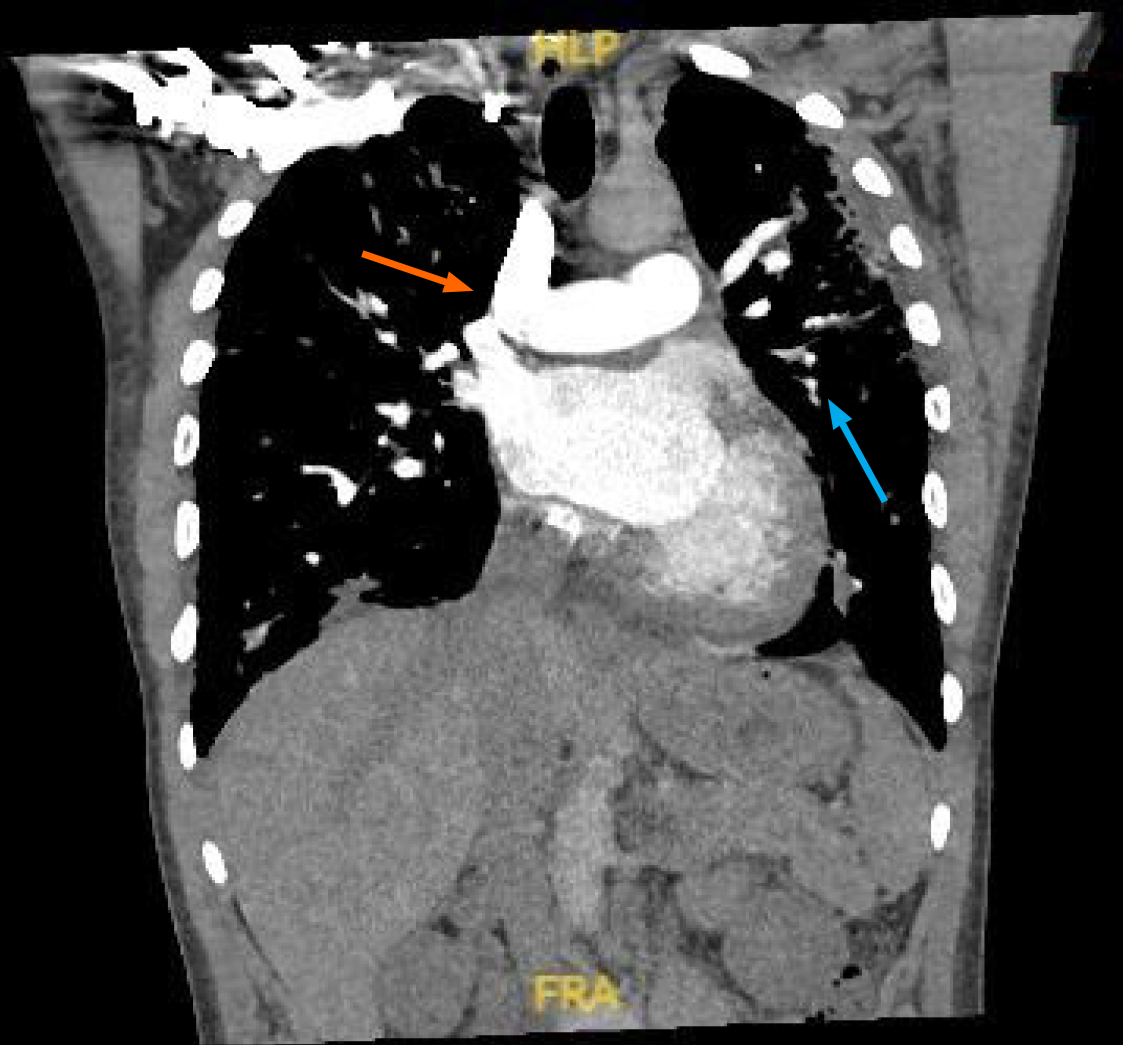

Telemetry showed a high premature ventricular complex (PVC) burden coupled with episodes of non-sustained ventricular tachycardia (NSVT). Electrocardiogram (ECG) showed frequent PVCs (Figure 2). Chest X-ray showed coarse reticulonodular infiltrates with diffuse lung nodules and bronchial wall thickening. Computed tomography angiogram (CTA) of the chest (Figure 3) demonstrated diffuse pulmonary nodules in all lung lobes and dilated main pulmonary trunk consistent with pulmonary hypertension.

Endoscopic bronchial ultrasound with bronchoalveolar lavage showed increased CD4: CD8 ratio without malignant cells. cMRI was performed and showed LV dilation with severe systolic dysfunction, global hypokinesis, and LGE (Figure 4). Whole body PET revealed patchy perfusion abnormalities in the basal to mid inferior wall and mid septal segments (Figure 5). It also revealed FDG uptake in the lungs without FDG uptake in the heart. Left heart catheterization showed normal coronary arteries, right sided pressures, pulmonary vascular resistance index, pulmonary capillary wedge, left ventricular end diastolic pressure, cardiac output, and valvular function.